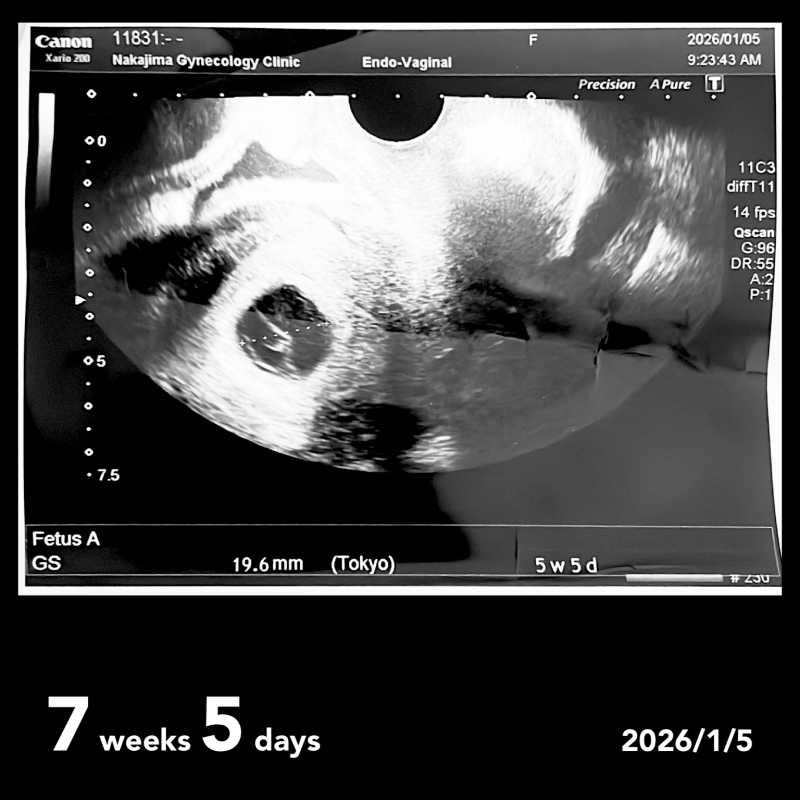

前回12月25日に6w1dで検診を受け、胎嚢15mm、 胎芽を確認できました。(5w1d相当)

1月5日に7w5d検診で、胎嚢19.6mmでしたが、胎芽が数ミリしか育っておらず、前回とあまり変わらないため、稽留流産の可能性が高いと言われました。(5w5d)心拍の確認もできていません。

来週再度検査をし、稽留流産で間違いないか判断するとのことでした。

お写真からですと、なかなかはっきりとしたことは明言できませんが、妊娠初期はまだ発育が不安定なこともありますし、週数のズレも見られることがよくありますよ。胎芽が小さいとご心配になるかと思うのですが、これから経過を見ていく中で、お子さんなりにしっかりと発育が見られるのであれば問題ありませんよ。